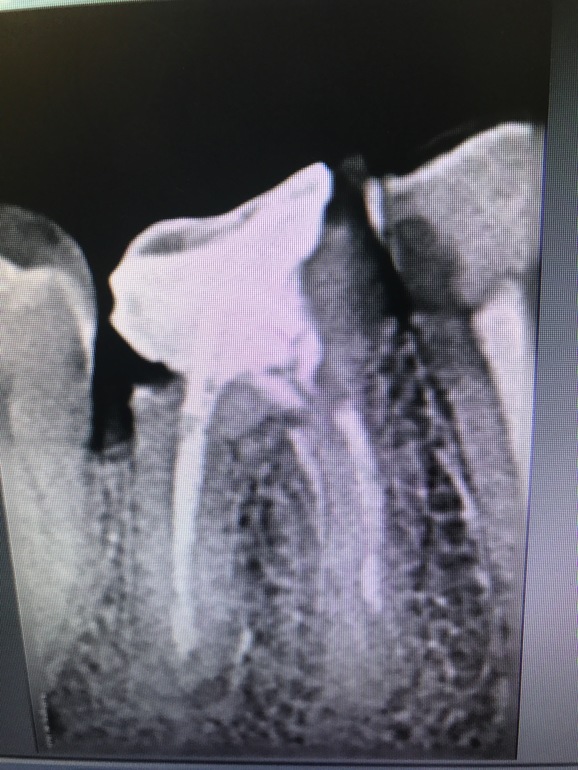

Можете по ренгену зуба сказать какой диагноз? и можно ли его вылечить?

Зуб выглядит плохо. Сильно разрушен, возможно, будет стоять речь об удалении. На соседний обратите внимание, на нем огромная полость на контакте, возможно, с захватом корня(.

Ощущение, что этот зуб вам приговорят. Впечатление, что часть стенки ушла с частью корня. Нужно было накрывать коронкой для сохранности.